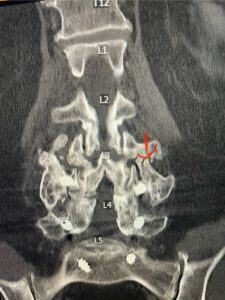

Fig 2: Coronal lumbar CT demonstrating L4-S1 fusion with instrumentation with some incomplete bony fusion to the L3-4 segment (red arrow)